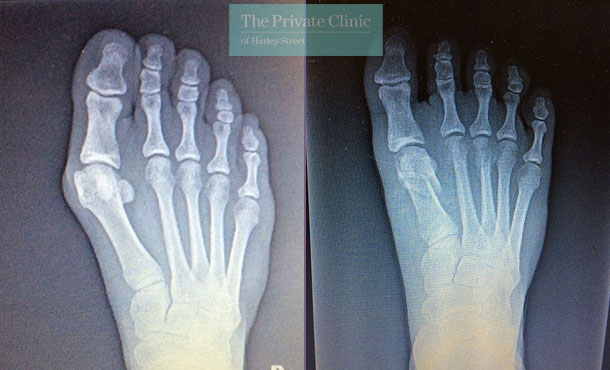

Bunion Removal Before and After Photos